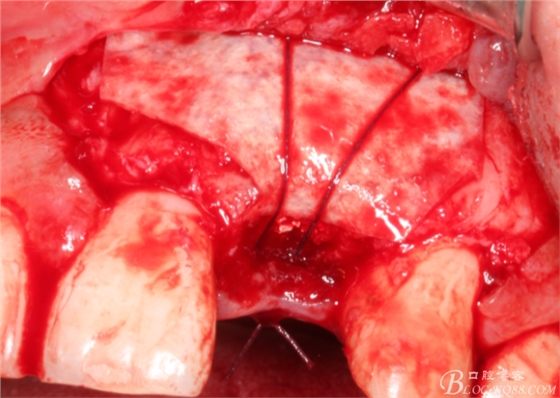

于是我果斷告知患者,手術(shù)失敗了,不能拖延,如不及時(shí)處理,炎癥繼續(xù)發(fā)展會(huì)很快波及鄰牙牙槽骨。患者接受我的建議。切開翻瓣,骨粉及生物膜消失了,骨吸收嚴(yán)重,幸運(yùn)的是,因?yàn)樘幚砑皶r(shí),鄰牙骨支持依然存在。

徹底掻刮。